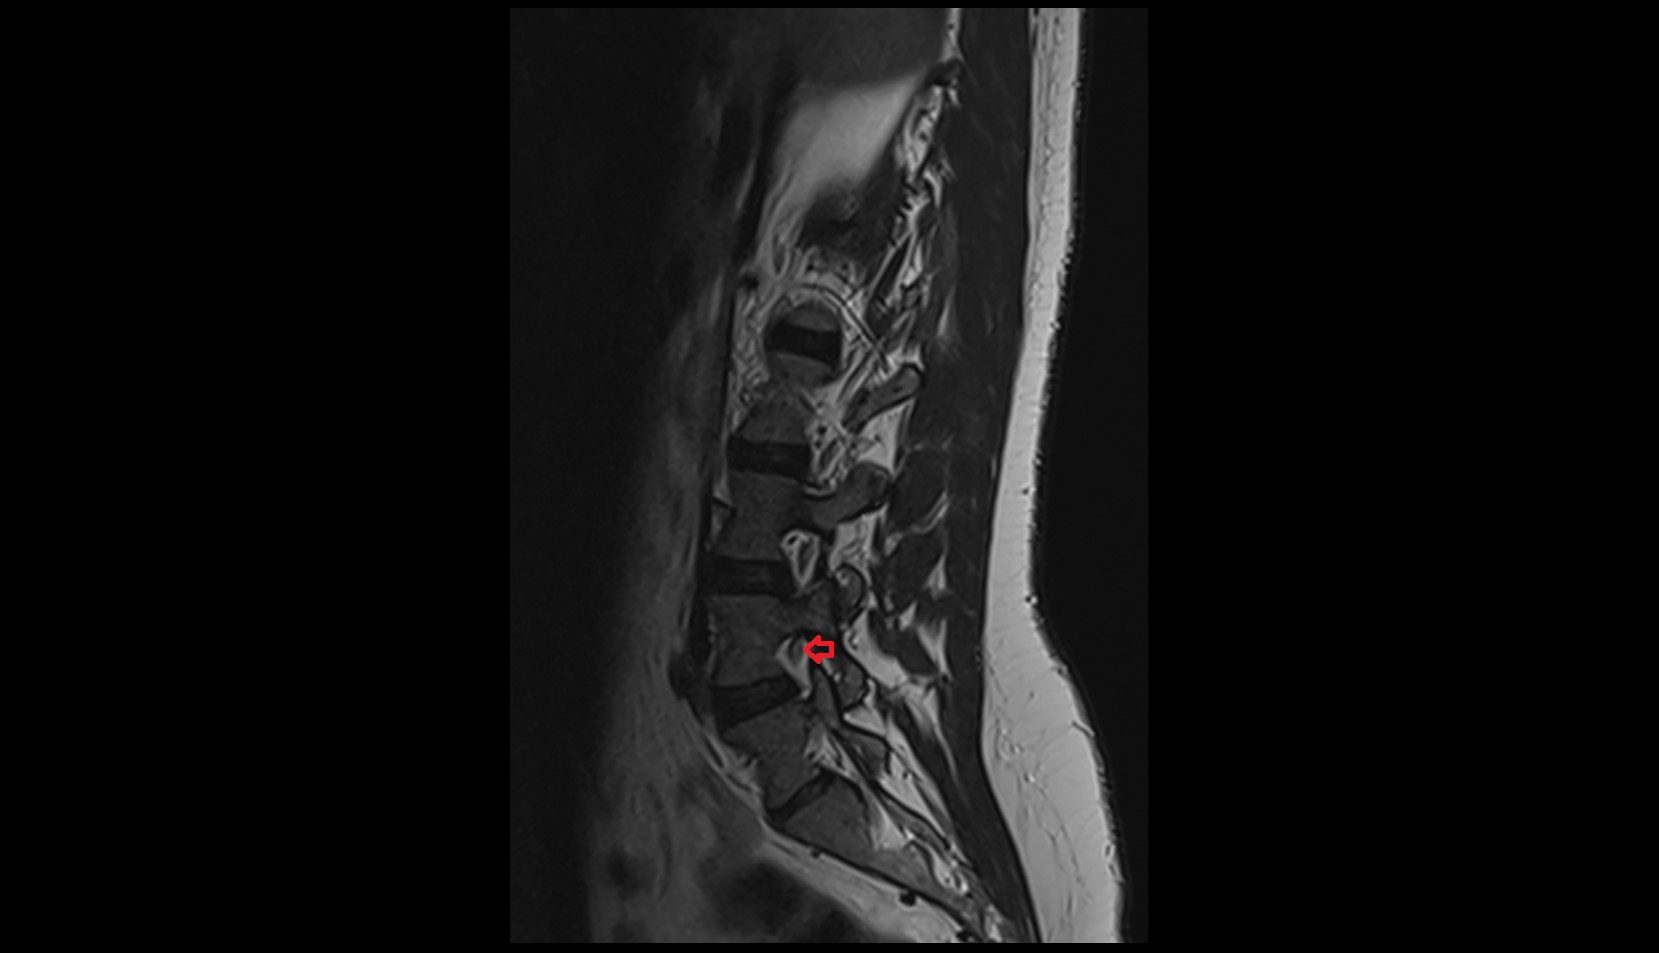

- Spinal cord

- Conus medullaris

- Cauda equina

- Intervertebral Disc